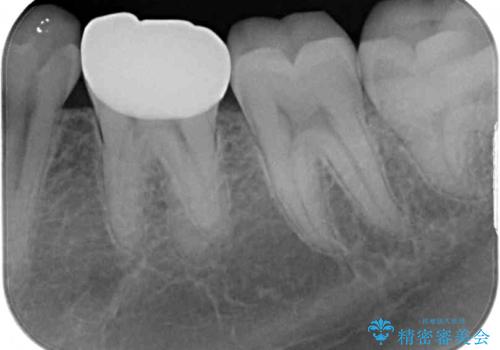

- 下顎左右奥歯に虫歯で痛みを感じるとのことで来院された患者様です。

むし歯が大きく、神経を取り除く可能性があることを理解いただいた上で虫歯を取り除き、その後はオールセラミッククラウンにて補綴することとしました。

虫歯除去後に痛みは収まり、神経も保存することができました。

変色していた歯もセラミッククラウンで自然な色合いとなり、患者様には大変満足していただきました。